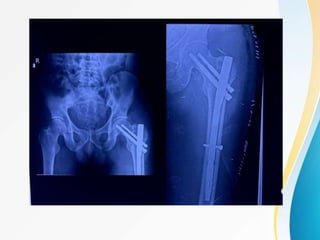

SLIDING HIP SCREW SHS :

DYNAMIC HIP SCREW :

• PRINCIPLE : Controlled collapse

• Dynamic action reduces the incidence of screw

cut out and penetration of screw into hip joint .

• Used for Stable per-trochanteric fracture .

• Lateral cortical wall of the proximal femur should

be intact ( pre-requisite).

• If not intact , DHS + TSP ( trochanteric

stabilisation plate ) should be used .

SHS :